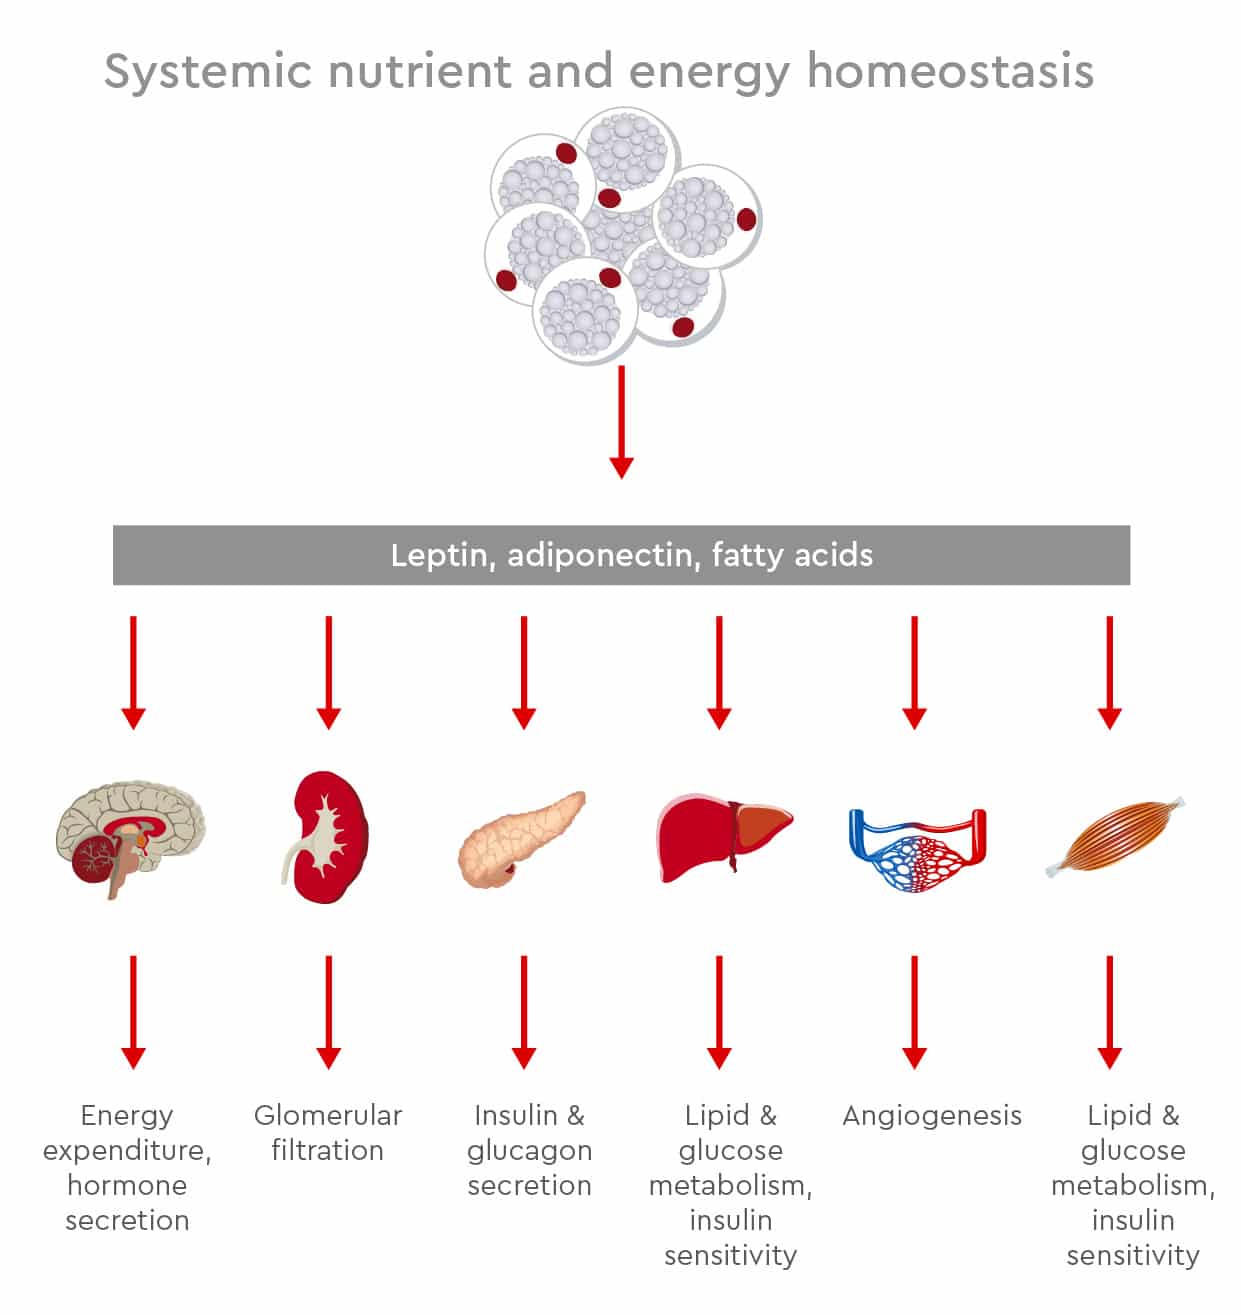

Adipocytes support metabolic homeostasis by coordinating energy storage, energy release, endocrine signalling, and inflammatory responses. Through these functions, adipose tissue helps the body adapt to changes in nutrient availability and energy demand.

White adipocytes store excess energy as triglycerides and release fatty acids when energy is needed. At the same time, adipocytes secrete adipokines and cytokines that influence appetite, insulin sensitivity, inflammation, cardiovascular function, and tissue remodelling.

Figure 2: Adipose tissue contributes to systemic nutrient and energy homeostasis by regulating lipid storage, lipid release, endocrine signalling, and inflammatory responses. When these processes become disrupted, adipose tissue dysfunction can affect metabolic organs such as the liver, muscle, heart, and pancreas.